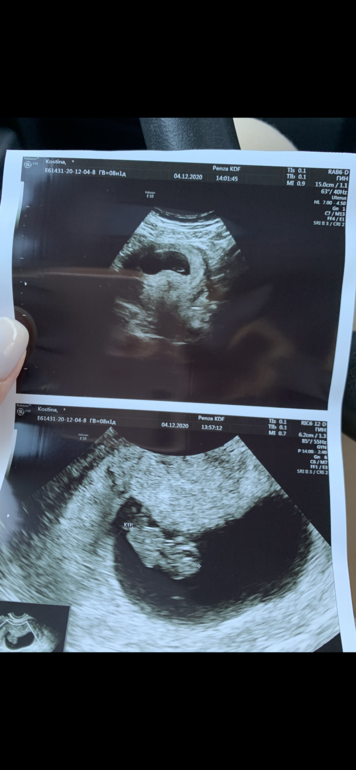

Узи делали и трансвагинально и абдоминально, честно говоря не знаю какая фотка откуда, не подскажите кто у нас будет?)